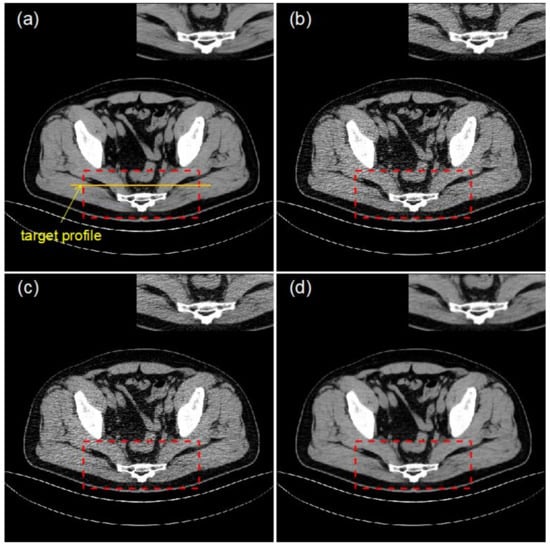

4.2. Clinical Data Experiments

| LDCT | Bicubic | RFSR | RFSR 2nd | RFSR 5th | |

|---|---|---|---|---|---|

| PSNR(dB) | 21.65 | 26.23 | 36.05 | 37.03 | 34.08 |

| SSIM | 0.75 | 0.80 | 0.92 | 0.95 | 0.86 |